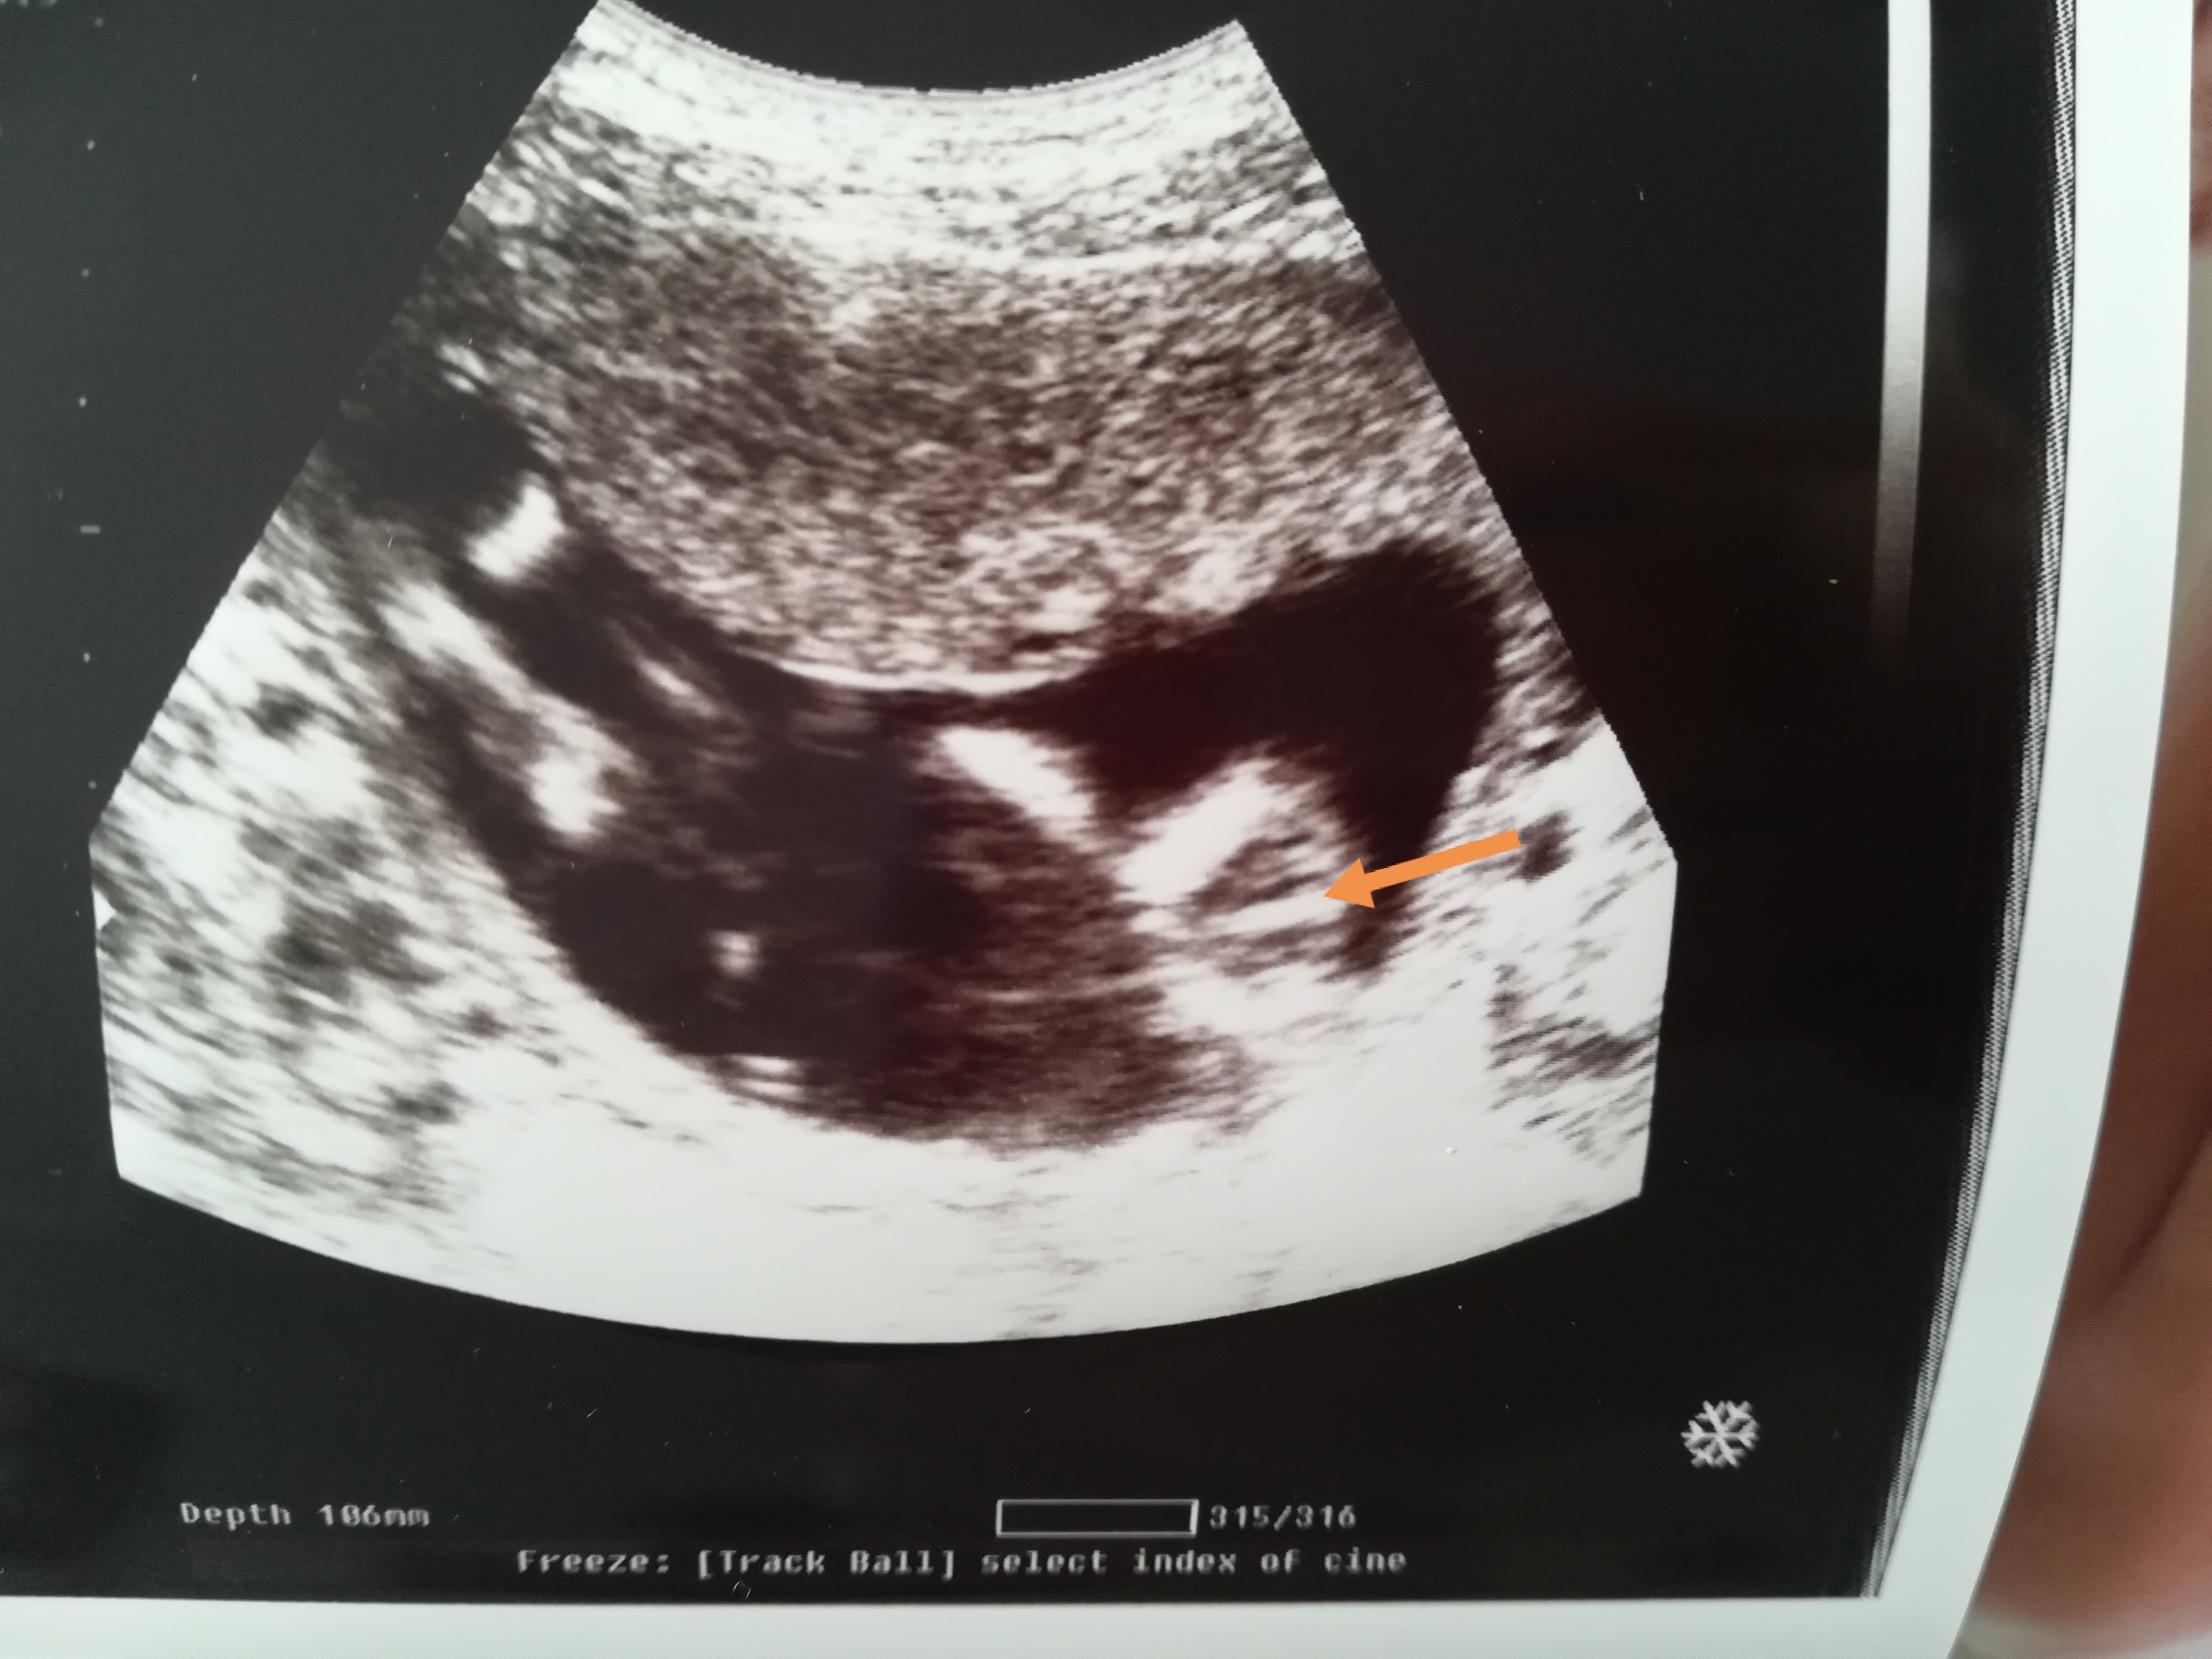

Oby badania wyszły dobrze. Dla lekarza zawsze coś niewinnie brzmi a Ty już masz pewnie stresu po same uszy. Co do spojenia, przy blizniakach na pewno masz dużo ciężej. Mnie już boli spojenie, nie wiem jak boli rozejscie ale chyba powinnaś leżeć?A jakoś tak przez chwilę było tu dziwnie podczas przepychanek kto może mieć dostęp do zamkniętego forum a kto nie ,że coraz rzadziej tu zaglądałam. Ogólnie jestem już po usg połówkowym na którym gin potwierdził płeć z usg z 12 tygodnia czyli 2 chłopców chociaż w 15 tygodniu miała być jedna dziewczynka. Chłopcy w 19w3d ważyli po 290 g. Jeden z chłopców ma w lewej komorze ognisko hyperechogenne lekarz mówił że to nic takiego ale mam mieć echo serca płodu 21 marca . Niestety chyba mam objawy rozejścia spojenia łonowego . Nie jestem w stanie chodzić siedzieć ani podnosić nic ciężkiego.

A jakoś tak przez chwilę było tu dziwnie podczas przepychanek kto może mieć dostęp do zamkniętego forum a kto nie ,że coraz rzadziej tu zaglądałam. Ogólnie jestem już po usg połówkowym na którym gin potwierdził płeć z usg z 12 tygodnia czyli 2 chłopców chociaż w 15 tygodniu miała być jedna dziewczynka. Chłopcy w 19w3d ważyli po 290 g. Jeden z chłopców ma w lewej komorze ognisko hyperechogenne lekarz mówił że to nic takiego ale mam mieć echo serca płodu 21 marca . Niestety chyba mam objawy rozejścia spojenia łonowego . Nie jestem w stanie chodzić siedzieć ani podnosić nic ciężkiego.